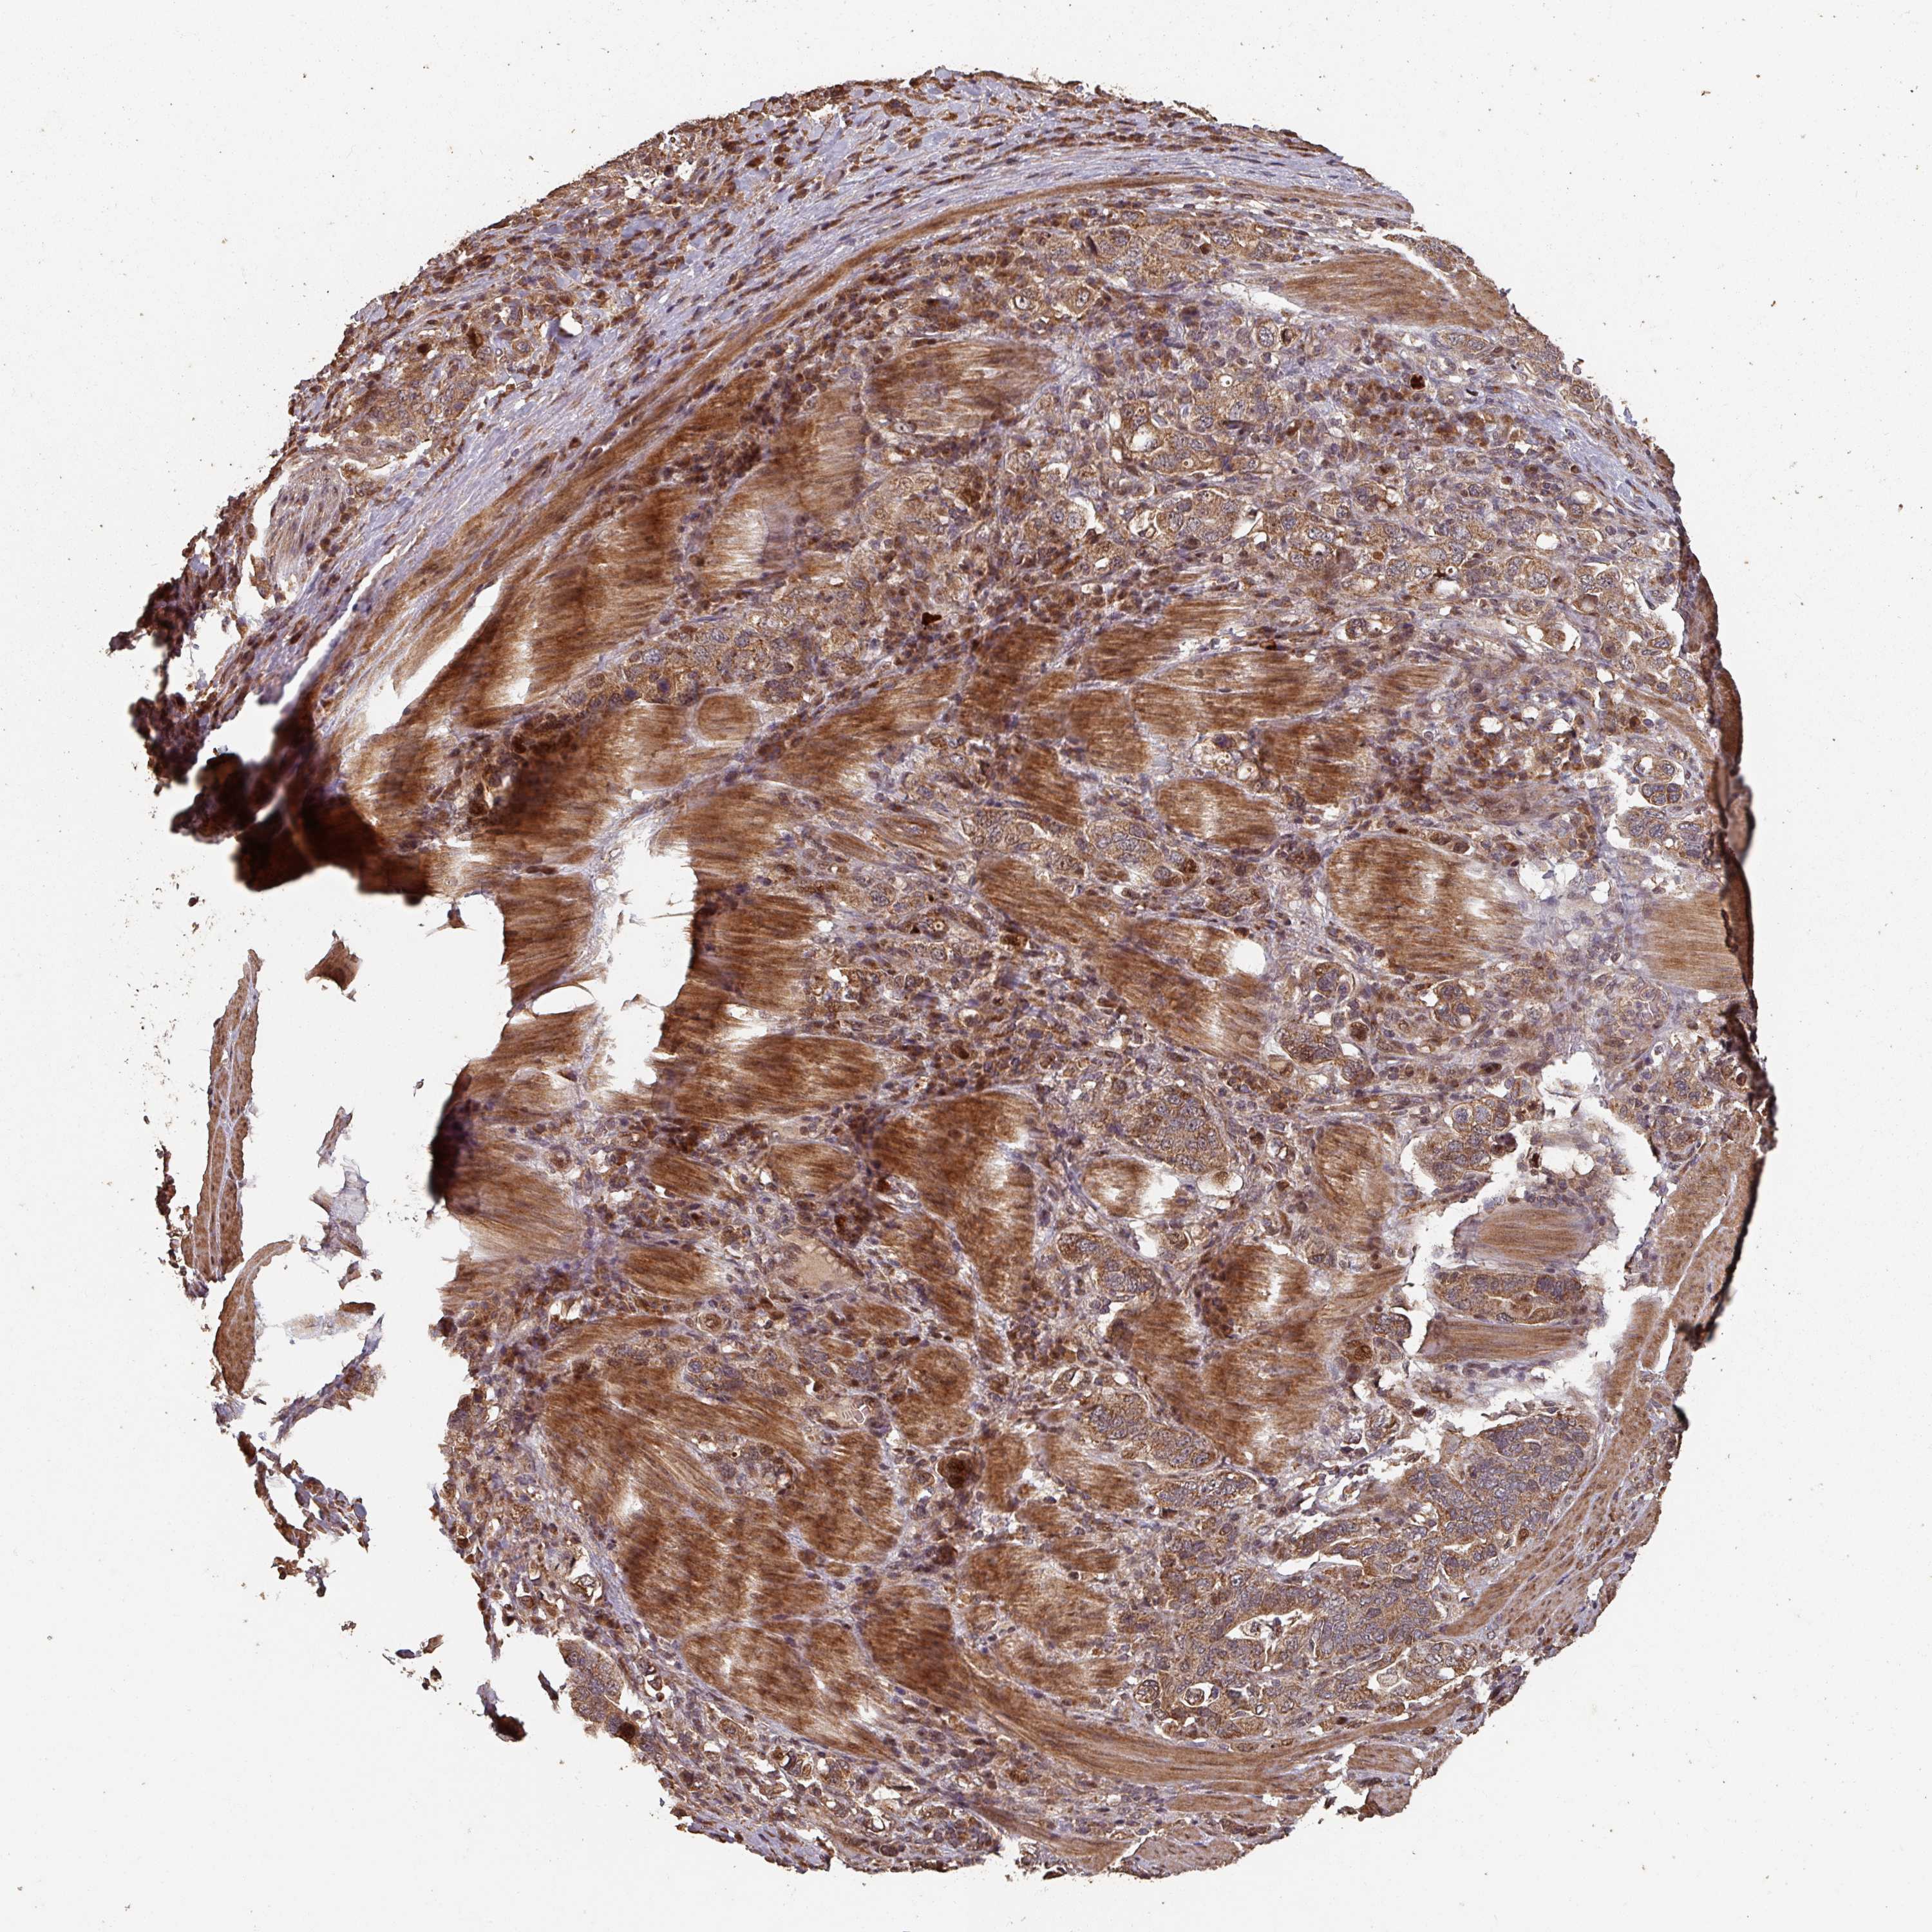

STOMACH CANCER - Protein expressioni

A mouse-over function shows sample information and annotation data. Click on an image to view it in a full screen mode. Samples can be filtered based on level of antibody staining by selecting one or several of the following categories: high, medium, low and not detected. The assay and annotation is described here.

Note that samples used for immunohistochemistry by the Human Protein Atlas do not correspond to samples in the TCGA dataset.

Antibody stainingi

Antibody staining in the annotated cell types in the current human tissue is reported as not detected, low, medium, or high, based on conventional immunohistochemistry profiling in selected tissues. This score is based on the combination of the staining intensity and fraction of stained cells.

Each image is clickable and will lead to virtual microscopy that enables deeper exploration of all samples and also displays staining intensity scores, fraction scores and subcellular localization as well as patient and tissue information for each sample.

Antibody HPA051123

Staining

High

Medium

Low

Not detected

Intensity

Strong

Moderate

Weak

Negative

Quantity

>75%

75%-25%

<25%

None

Location

Nuclear

Cytoplasmic/membranous

Cytoplasmic/membranous,nuclear

Adenocarcinoma, NOS